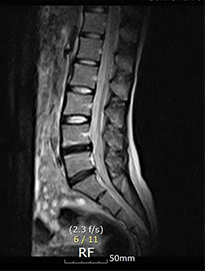

디스크내장증을 다른 말로 블랙디스크(black disc)라고 부르기도 하는데, MRI 검사 영상을 보면 디스크 부분이 검게 보이기 때문에 블랙디스크라고 부릅니다. 디스크 내의 수분이 빠지면서 탄성이 떨어지고 퇴행이 진행되어 검게 보이는 것인데요. 이처럼 아직 디스크가 탈출하지 않아 방사통이나 저림 증상이 없다고 하더라도 이미 퇴행이 진행된 상태라 이는 퇴행성 디스크의 일종이라 볼 수 있습니다.

디스크내장증은 디스크가 탈출된 것이 아닌 디스크만 퇴행된 것이므로, MRI영상으로 보면 신경이 지나가는길이 깨끗하다는 것이 특징입니다.